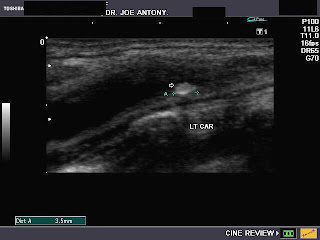

These ultrasound images of a young, asymptomatic adult female patient reveal multiple calcific plaques of the common carotid arteries of both sides. The intimal plaques measure 1.5 to 4mm. in size. These sonographic images are diagnostic of dystrophic calcification of the intima of the carotid arteries. Such lesions are very unlikely to cause stroke or thromboembolic events and are hence of little significance. All ultrasound images taken with a Nemio - XG ultrasound system, by Joe Antony, MD, India.References:1) http://www.evtodayarchive.com/03_archive/0902/et0902_15.html (a good article.. free).